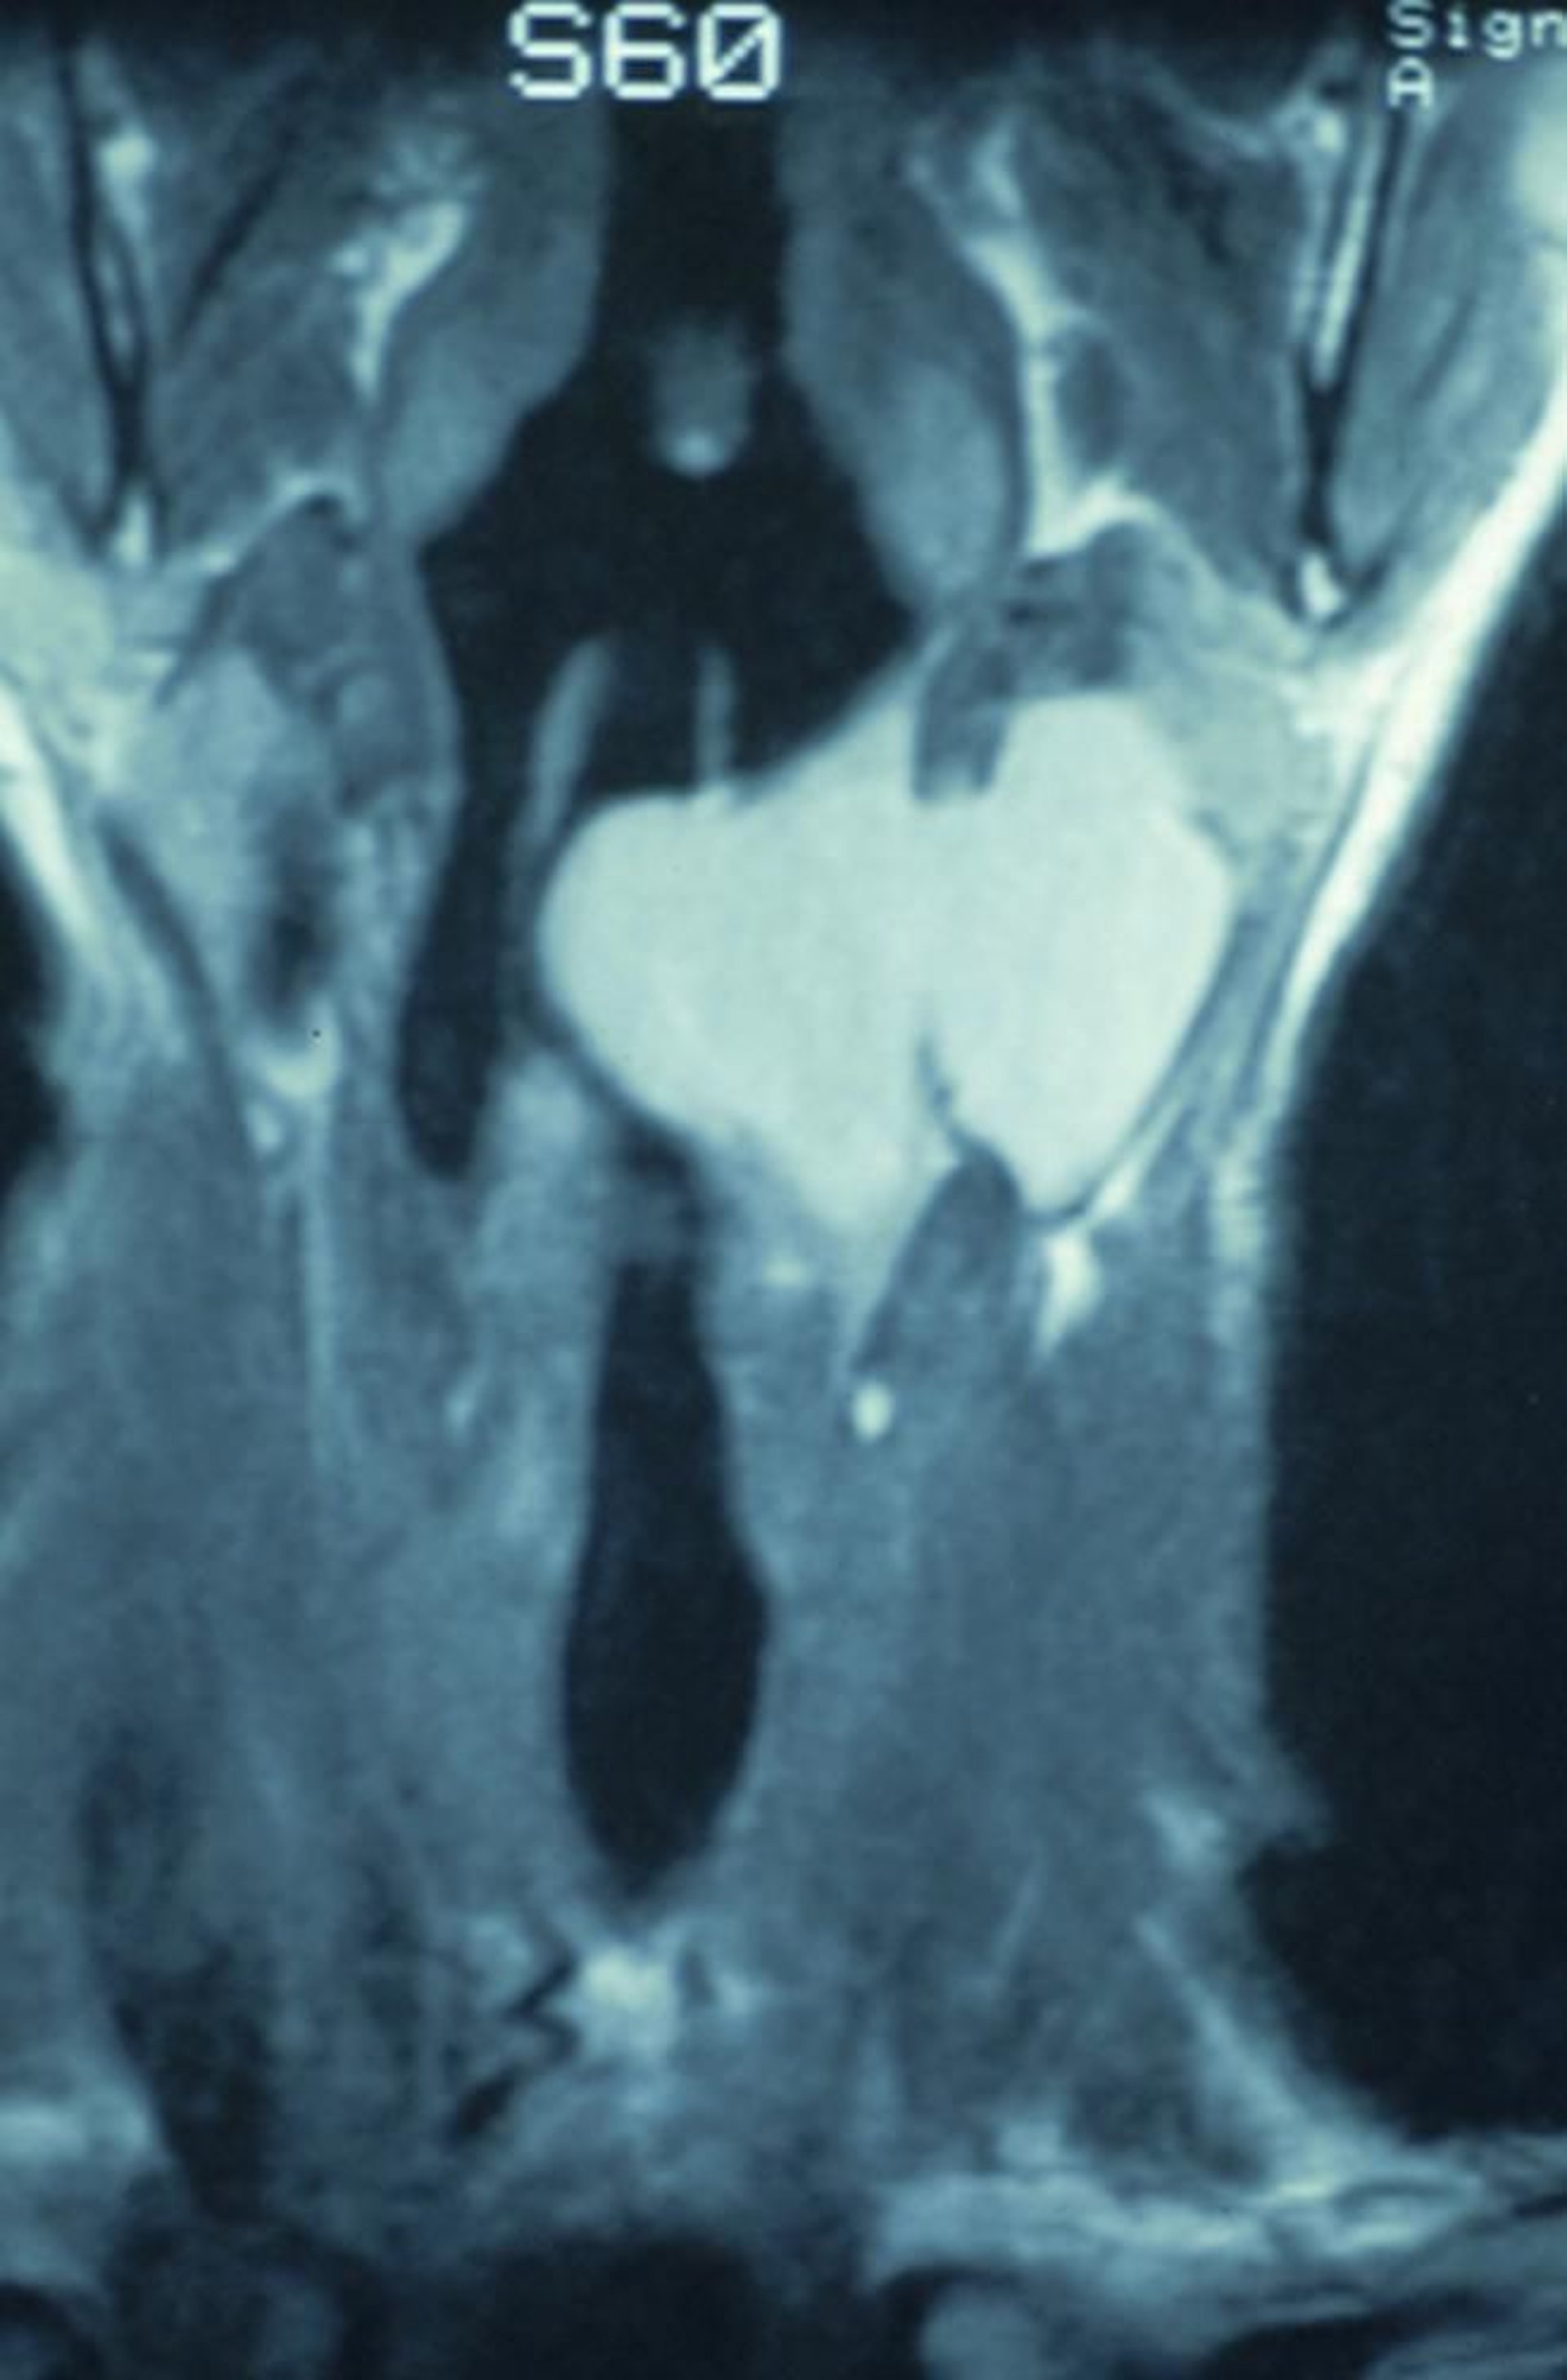

Kombinierte Laryngozele

Diese koronale CT-Aufnahme zeigt eine kombinierte Laryngozele, die im Larynx beginnt und sich durch die Thyreoidea erstreckt und eine Raumforderung im Hals verursacht.

Image provided by Clarence T. Sasaki, MD.